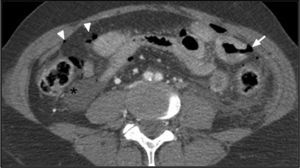

A 31-year-old male was taken to the emergency service of our hospital with multiple trauma caused by a traffic accident. The whole body CT scan revealed hemoperitoneum, slight pneumoperitoneum and diffuse intestinal loop thickening (Fig. 1), Intravenous contrast (IVC) uptake was seen to be absent in a jejunal loop, consistent with hypoperfusion (Fig. 2), and intestinal perforation foci (Fig. 1). Emergency surgery confirmed the ischemic loop secondary to the avulsion of small-caliber mesenteric vessels. The avulsion of mesenteric vessels secondary to closed abdominal trauma is infrequent, particularly in the absence of associated solid organ damage. Although mesenteric hematoma and the extravasation of IVC constitute more specific signs, the condition should be suspected in the presence of an intestinal segment showing hypoperfusion with a thickened wall, pneumoperitoneum and hemoperitoneum without solid organ damage.